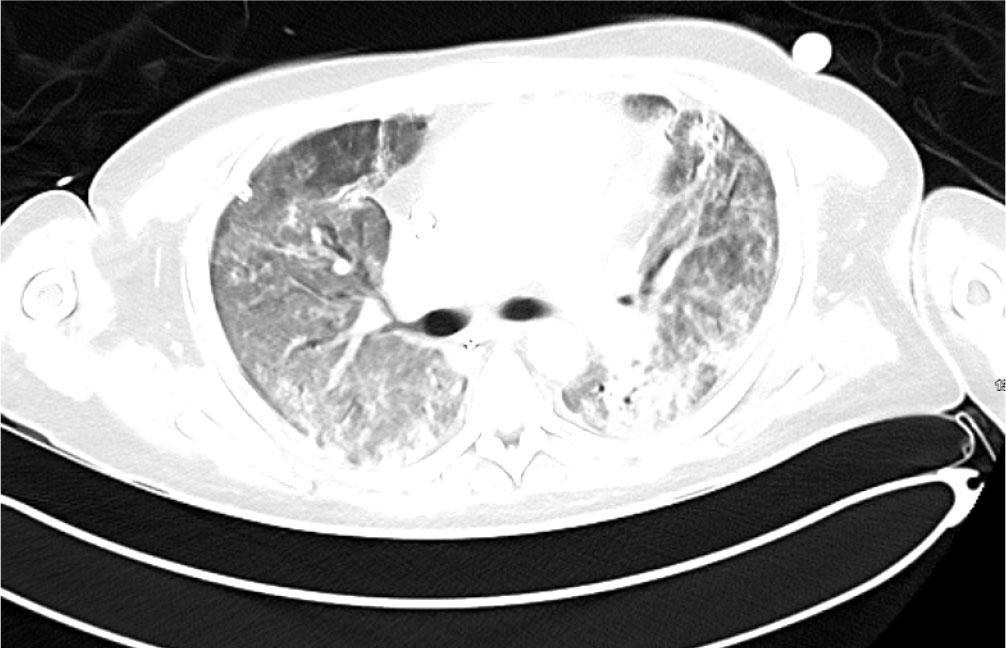

The patient received plasma exchange after consultation with the Haematology team, with a total of 5 sessions completed. While on ECMO he received another 1g rituximab and 2 further doses cyclophosphamide (500 mg I.V.). Gradually the patient improved. He tolerated 24 hours off sweep gas flow and was successfully decannulated from ECMO after 37 days. Ventilatory requirements immediately post ECMO decannulation showed acceptable peak pressures of 18 cmH2O with FiO2 0.4 (PEEP 6 cmHO + Pressure support 10cm H2O). A CT was repeated on Day 39 shortly after ECMO was discontinued which showed bilateral improvement in both nodular and ground glass opacifications (Figure3). There was evidence of early traction bronchiectasis.

CT Thorax performed on Day 39 shortly after discontinuation of ECMO showed nodular and ground glass opacification which have improved significantly in the interim. There was some early traction bronchiectasis.